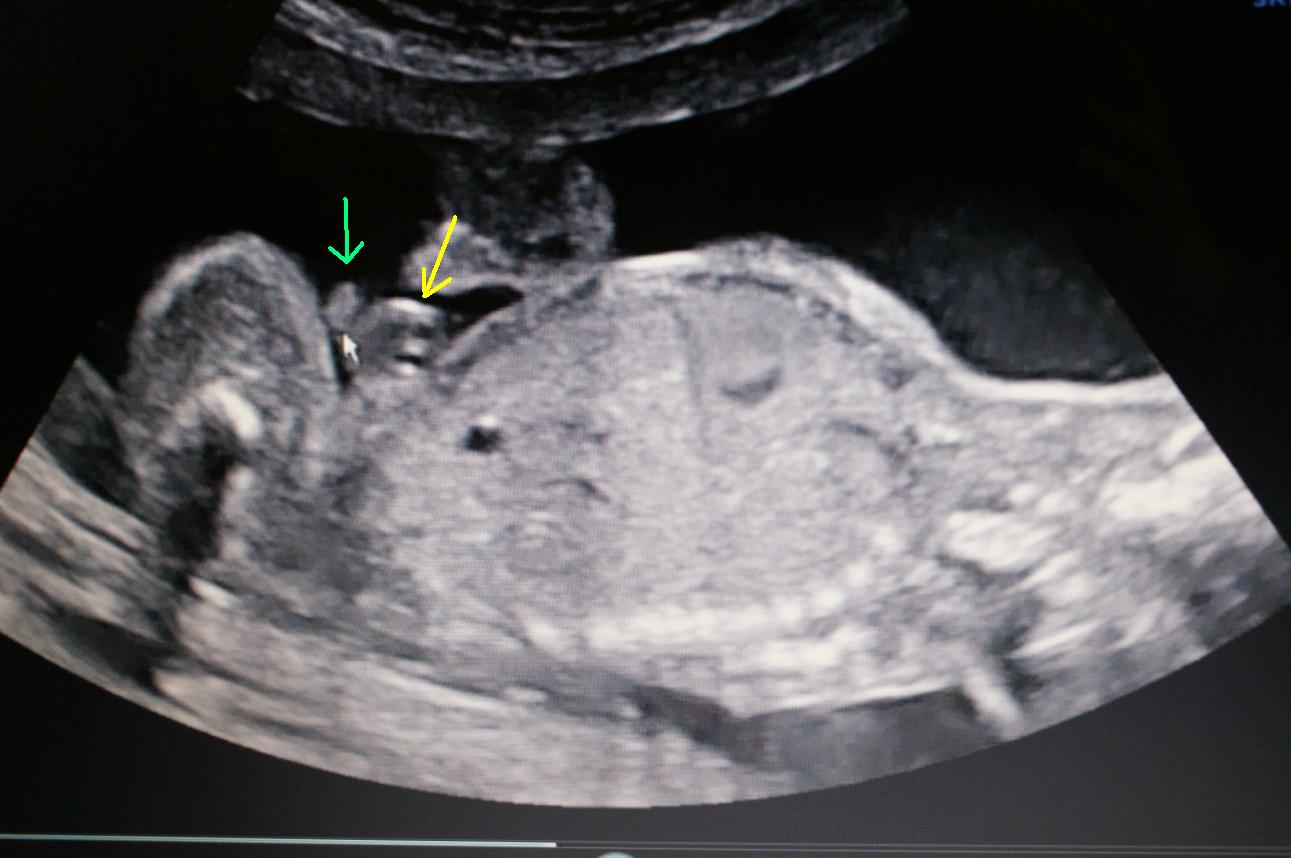

Is this a Boy or Girl Please Help

Hi i had my 20 week scan and they couldnt tell for sure if it was a boy or girl as the legs where closed and the cord was between its legs but she said she thinks boy but i went through ultrasound and could see boy and girl bits (this baby really dosent want to tell me) the ultrasound lady wasnt too helpful wouldnt confirm for sure and didnt really try and get a good look she pointed out what she thinks is a boy but i compare them to my other boys and others and it dosent look anything like it i have put 2 up that she pointed to that is from side and i found another one that she had done from behind but far back but when i look at it you can see a y which i have pointed at it in red.I thought if you saw a y it is a girl i have had alot of mixed reply's so i would love your thought on what you think and why you think it thanks in advanced to everyone who reply and to those who already have to my Nub